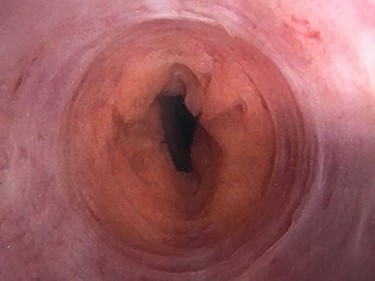

The patient underwent further evaluation with imaging including renal ultrasound, which was normal. Flexible cystourethroscopy demonstrated a circumferential urethral mass concerning for urothelial carcinoma (Fig. 1), which was biopsied with histopathology negative for urothelial carcinoma but positive for amyloid protein deposition. Examination of the external genitalia was unremarkable and there was no palpable induration along the ventral penile shaft. Systemic workup for additional manifestations of amyloidosis was negative. Imaging with retrograde urethrography (RUG) demonstrated an ~2 cm segment of urethral stenosis in the penile urethra (Fig. 2).

Endoscopic visualization of circumferential amyloid protein deposition causing urethral luminal narrowing.